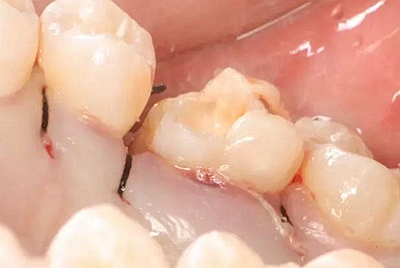

改良垂直褥式縫合關閉傷口,傷口無明顯滲血,高嵌體預備完畢后,硅橡膠取模,見邊緣清晰。灌注模型,模型上3MZ350XT分層堆塑高嵌體。

一周后拆除縫線,試戴高嵌體,試戴合適后雙固化粘結。調(diào)合,拋光。